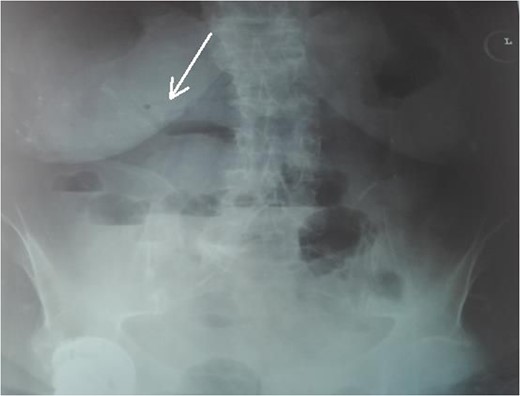

An 87-year-female patient was admitted to emergency department complaining about vomiting for the past 7 days with mild abdominal pain. The patient was hemodynamically stable, had sluggish bowel sounds and soft abdominal wall with mild tenderness. The patient also suffered from atrial fibrillation, heart failure, myelodysplastic syndrome, hiatus hernia and cholelithiasis. The findings of the laboratory tests were unremarkable. Plain chest and abdominal radiograms revealed hiatus hernia with gastric dilation (Fig. 1), a few air-fluid levels and pneumobilia, with delineation of extrahepatic and intrahepatic bile ducts by air (Fig. 2). A nasogastric tube was inserted, which drained biliary content. An abdominal computed tomography (CT) scan revealed the presence of air in the intrahepatic bile ducts, free air and leakage of oral contrast agent in the hepatic hilum and subhepatic space and an impacted gallstone in the third portion of the duodenum (Figs 3 and 4). The diagnosis of cholecystoenteric fistula and proximal gallstone ileus was set.

Abdominal CT scan (axial plane). The arrow shows the impacted gallstone.